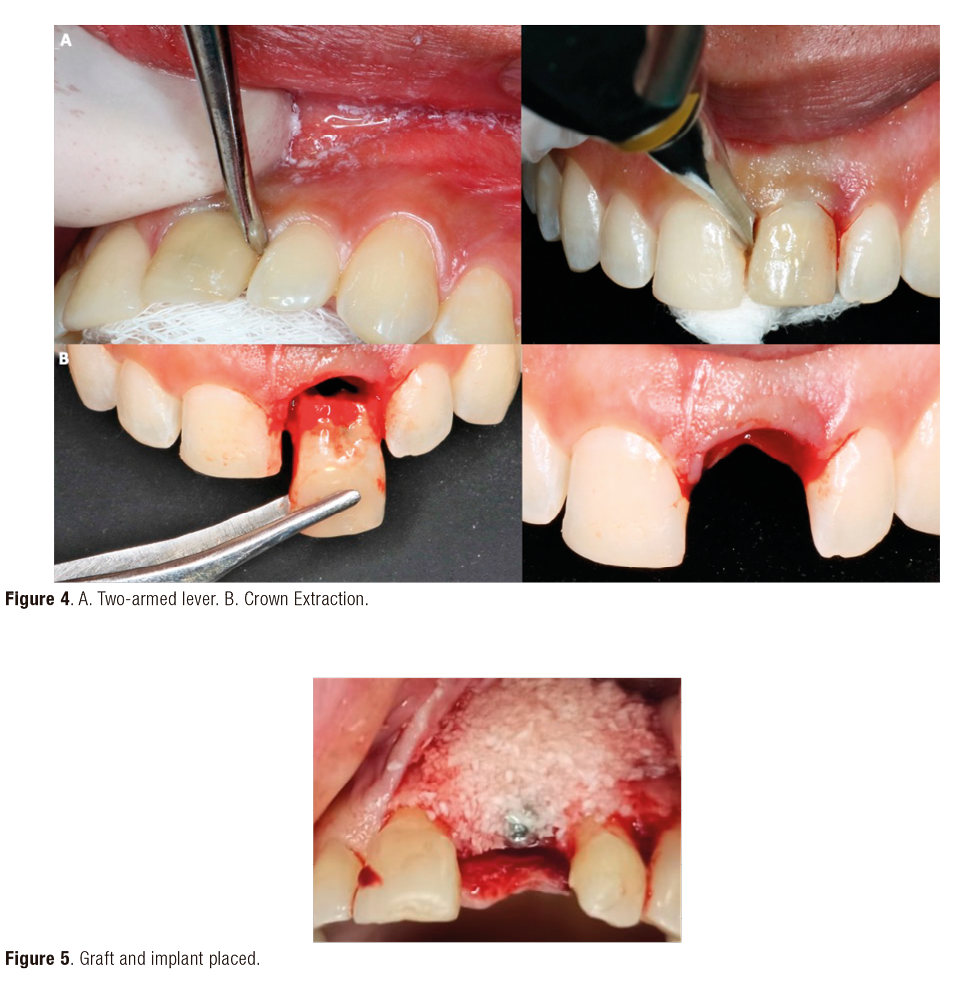

A 24-year-old male patient who required extraction of the upper left central incisor due to a corono-radicular fracture, reason for which is requested, panoramic radiography and cone beam, in which, as in the immediately previous case, the extraction was planned using a two-armed lever as an atraumatic alveolar preservation technique. During the clinical examination, it was observed at the level of the upper left central incisor, resin filling of 4 surfaces and slight redness was evident at the gingival margin (Figure 3.A and Figure 3.B). The extraction procedure was initiated by applying the strength of the two-arm lever, the straight elevator is in a horizontal position resting on the mesial and distal surfaces have the greatest possible palatal rest and resistance in the mesial and/or disto-vestibular areas; that generates an extrusive dental dislocation that combined with the vestibular palatine grip with the left hand helps to avoid compromising the vestibular table, then it is produced in the first instance, tooth crown extraction (Figure 4.A and Figure 4.B), by the corono-radicular fracture already mentioned, then its proceed to the dental root´s extraction, using lever of the second degree, without compromising the vestibular and palatal tables. Once confirmed the integrity of the vestibular wall and the gingival biotype: type I socket, 1cc of Puros® particulate cortical bone (250-1000 microns) is used for the graft. Subsequently, Zimmer TSV 3.7 * 13mm implant was placed (Figure 5). The implant was prepared and placed 2.5mm from the gingival margin to achieve primary fixation, a surgical cover screw was placed, the cavity was occluded with a collagen membrane (CollaTape®) and sutured transverse and horizontally with acid polyglycolic 5-0, followed by a provisional restoration, finally, the patient is prescribed oral capsules of dicloxacillin 500mg and nimesulide tablets orally 100mg. After five months of clinical and radiographic controls, the second phase begins. The patient received a metallic ceramic crown with functional and aesthetic results after 18 months of continuous controls.